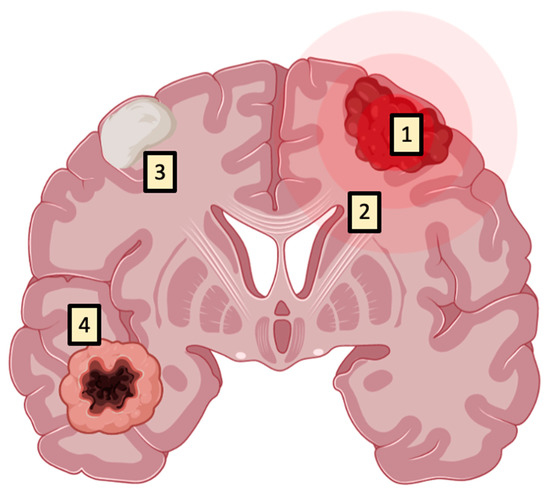

Fluorescence has also been observed in non-oncological settings, such as in multiple sclerosis, neurodegenerative diseases, and infectious conditions. Notably, all of these conditions share a conspicuous number of immune cells which, as mentioned before, can display fluorescence due to 5-ALA uptake and metabolism. In addition, the macroscopic fluorescence in bacterial brain abscesses could be explained by the bacteria capability to elaborate porphyrin precursors, since they are useful cofactors for their growth [19,20,21] (Figure 6).

Figure 6.

Even if 5-ALA is a highly tumor-specific tracer (1), fluorescence could be observed in normal anatomical structures such as the periventricular area (2) or in conditions or systemic inflammatory pathologies such as multiple sclerosis, brain abscesses (3), and other inflammatory diseases involving the brain, or in cases of radionecrosis (4) due to the presence of inflammatory infiltrates.